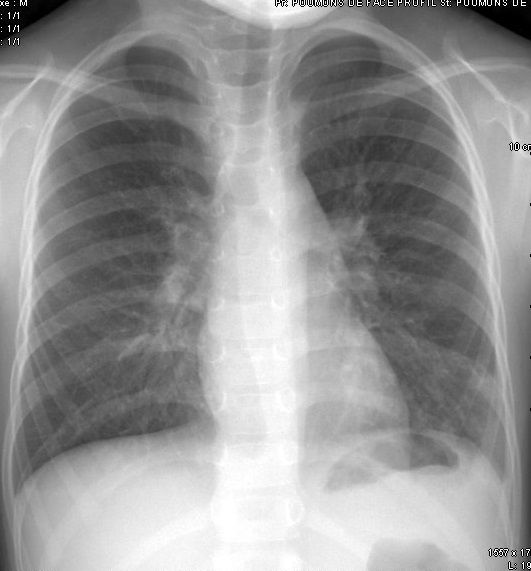

Il faut savoir qu'une radio des poumons délivre l'équivalent d'1-2 jours d'exposition aux rayons isonisants naturels